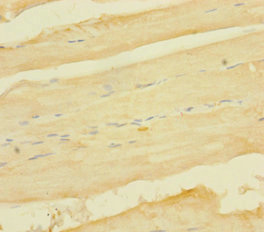

圖片:

應用范圍:ELISA, IHC

Application Recommended Dilution IHC 1:20-1:200 -